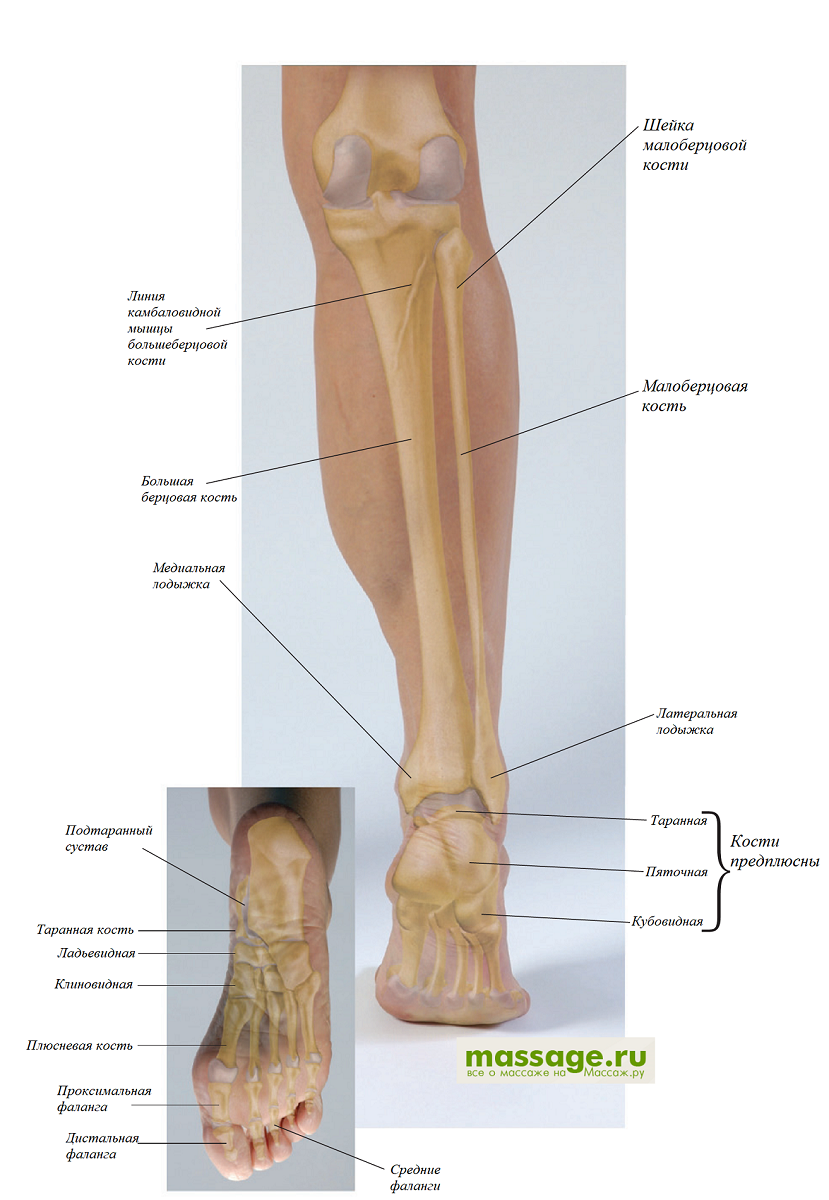

Анатомия фибулы: Подробные фотографии и схемы